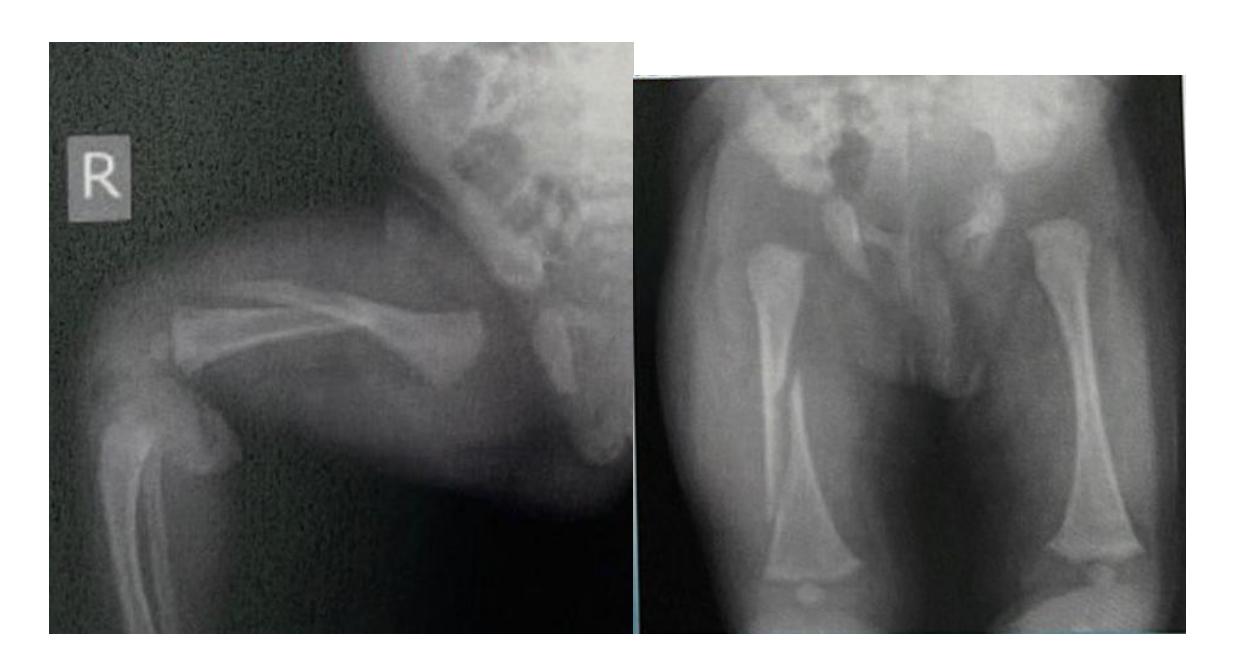

Q8/ What is the type of fracture shown in these pictures?

- A- Salter harris fracture II